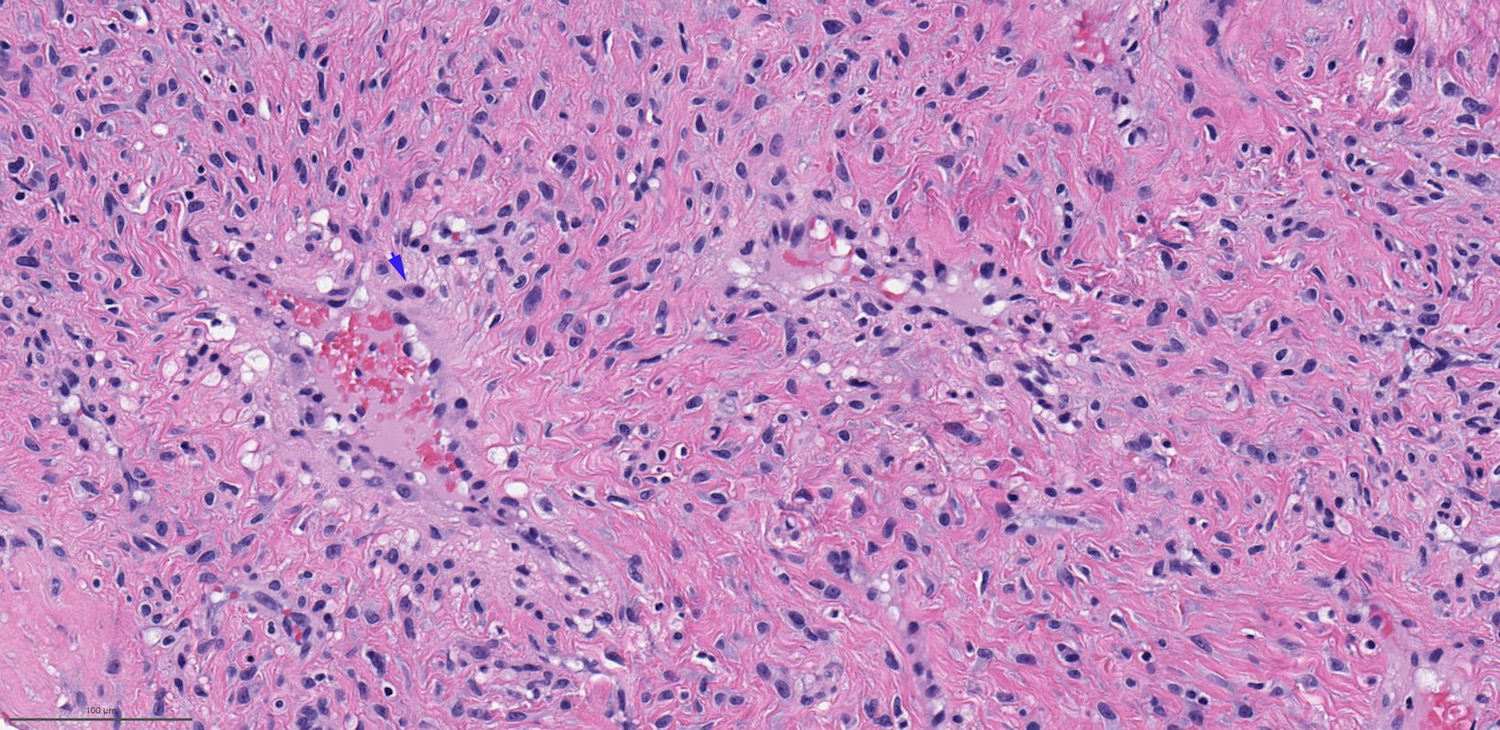

Microscopic (histologic) description

- Benign fibrovascular lesion composed of 2 components

- Vascular space of various sizes, ranging from dilated branching vessel of various thickness to slit-like capillaries

- Fibrous or collagenous stroma with fibroblasts

- Central area of the tumor is typically cellular, composed of fibroblasts or myofibroblasts with spindle, round or stellate morphology

- Stroma can be fibrous, edematous or collagenized

- Fibrinous thrombi may be seen in dilated vessels

- Frequently contain (abundant) mast cells

- Mitotic figures are usually absent

Microscopic (histologic) images

Contributed by Bin Xu, M.D., Ph.D.

Contributed by Kelly Magliocca, D.D.S., M.P.H.